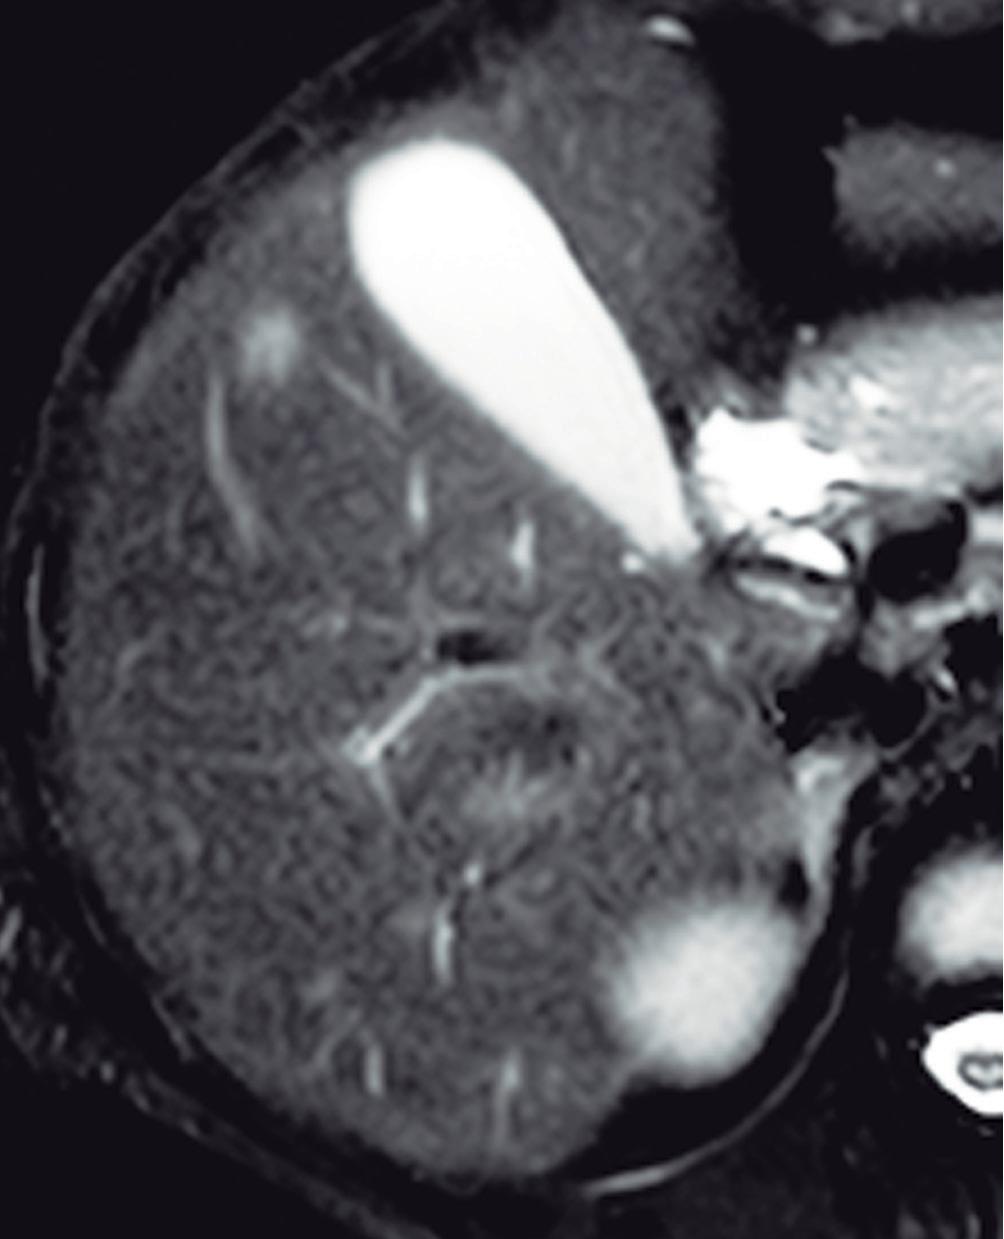

(Figura 1) En los hemangiomas de mayor tamaño el pasaje del contraste al centro de la lesión toma más tiempo e incluso no ocurre en aquellos más voluminosos.

En la RM los hemangiomas son lesiones con señal hipointensa en T1 e hiperintensa muy marcada en T2. Esta última característica los diferencia de otras lesiones benignas o malignas, con excepción de los quistes, que presentan señal más elevada debido a su contenido acuoso.1 El patrón de realce poscontraste es igual al que muestra la TC. (Figura 2) En la secuencia de difusión no presentan un patrón restrictivo, si bien pueden exhibir una señal brillante en valores b altos (parámetro que pondera la difusión); esto se debe al efecto brillo T2 y no a la restricción verdadera, por lo que el mapa del coeficiente de difusión aparente (ADC, por sus siglas en in-

A

glés) muestra señal y valores altos. En estudios con CHE son hipointensos en fase hepatobiliar ya que carecen de hepatocitos. Una potencial causa de error puede ocurrir en algunos hemangiomas pequeños que presenten un refuerzo precoz importante y que en fase de equilibrio (3 minutos) pueden presentarse hipointensos (pseudolavado). De esta manera podrían ser malinterpretados como un CHC.2 No obstante, la característica señal brillante de los hemangiomas en T2 es de utilidad para una tipificación correcta.

A: T1 post contraste en fase venosa portal; B, y fase de equilibrio; C: Muestran lesiones en segmentos IV y VI con una señal marcadamente hiperintensa en la secuencia T2 y

Lesiones benignas localizadas en el hígado desde la mirada de las imágenes Mariano Volpacchio Figura 1. Hemangioma en tomografía computada. Imágenes axiales de la TC sin contraste Figura 2. Hemangioma en la RM. Imágenes axiales de la RM en secuencia T2 con supresión grasa con el refuerzo similar a las estructuras vasculares de aspecto globular y progresivo en sucesivas fases. Nótese la heterogeneidad del hemangioma de mayor tamaño en segmento VI. A B C